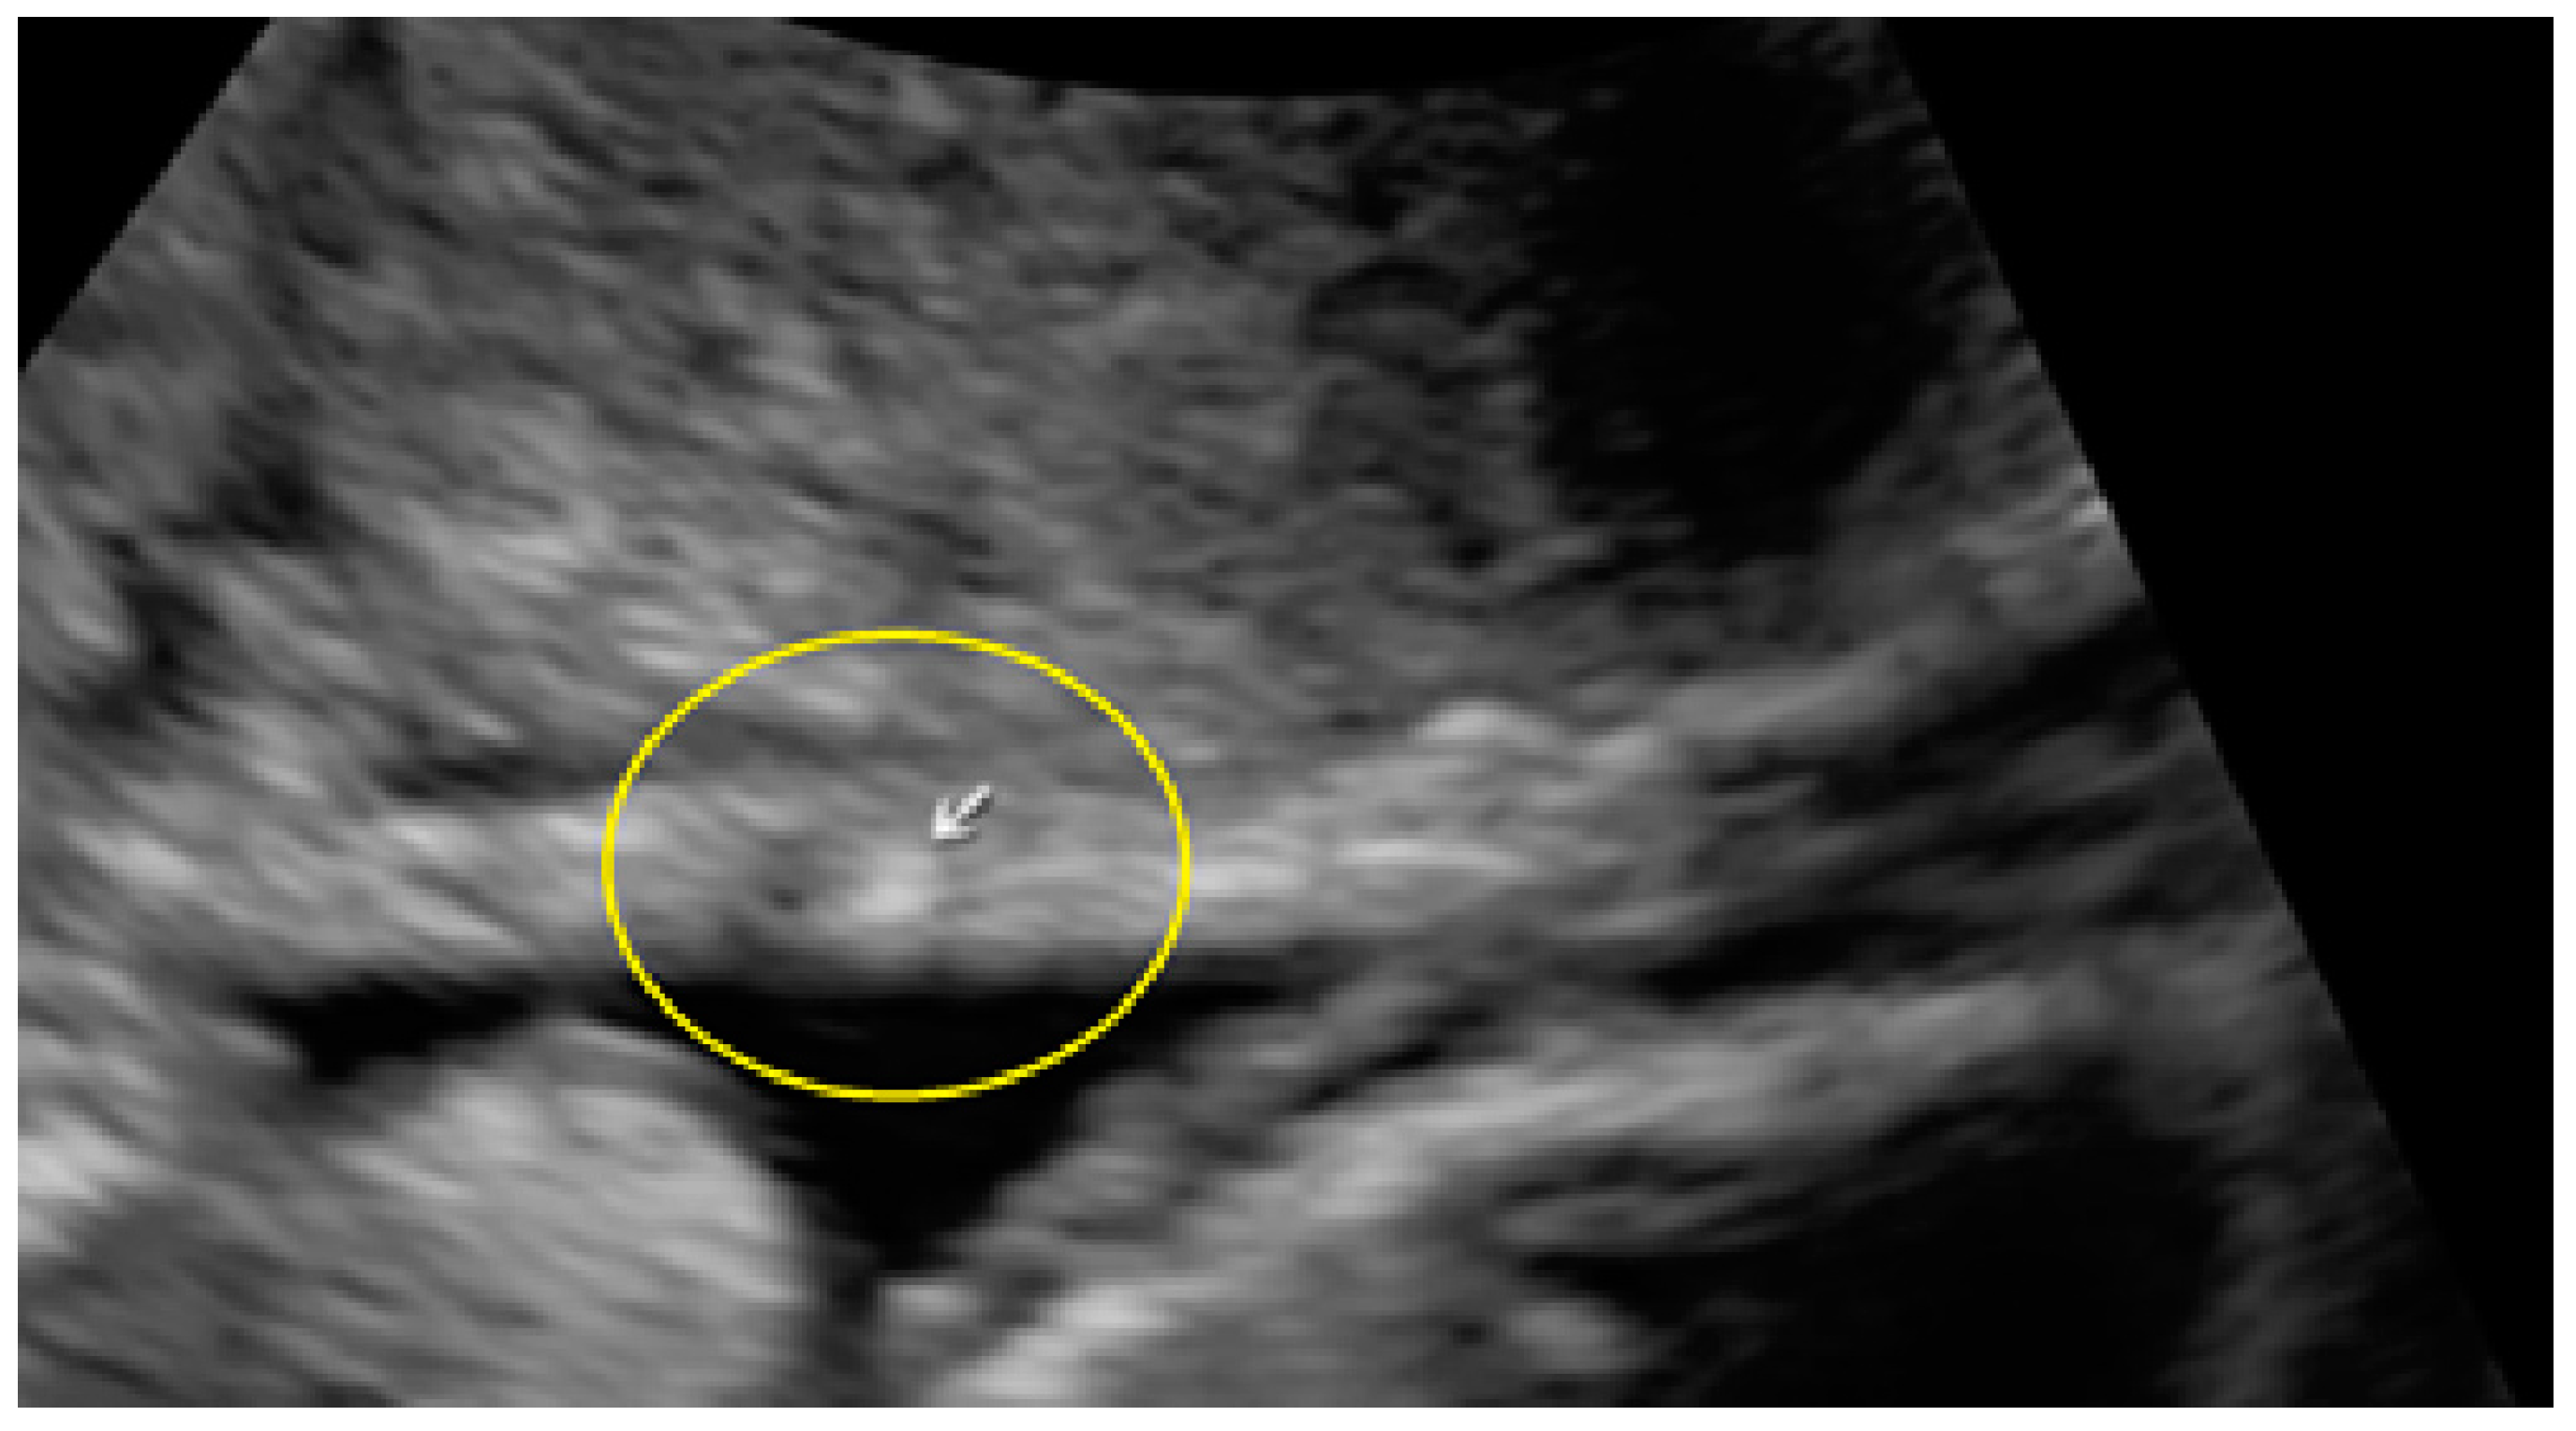

- The presence of hypoechogenic associated tissue (hypoechoic areas surrounding a small cyst area; we called this a “hat”). This tissue does not protrude or invaginate the peritoneal surface.

- The lesion may be convex, protruding from the peritoneal surface into the peritoneal cavity (we called this “bulging”), or it may appear as a concave defect in the peritoneum (we called this a “pocket”).

- The presence of hyperechoic foci (we called this a “pearl”).

- The presence of velamentous (filmy) adhesions associated to the lesion (we called this a “veil”).

3.2. Cystic Multiple Separate Lesions